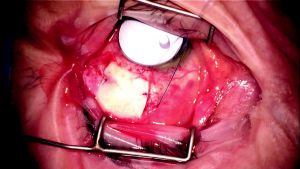

Covering the Tube With a Patch Graft

To prevent the tube from eroding through the overlying bulbar conjunctiva, it is strongly recommended to cover the exposed tube from the plate to the sclerostomy with a patch graft.[3] Different materials including donor sclera, donor cornea, or Tutoplast (New World Medical, Inc) can be used as a patch graft to cover the exposed tube. The most important portion of the tube requiring coverage with the patch graft is the site where the tube enters into the sclerostomy. The patch graft can be tacked down to the underlying sclera by using 2 to 4 7-0 polyglactin sutures (Figure 8- 5). When securing the patch graft to the underlying sclera, care should be taken not to penetrate the lumen of the tube.